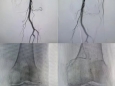

痔疮动脉栓塞术是基于“痔的血供主要来源于直肠上动脉分支”的解剖学基础,通过介入微创技术,经股动脉穿刺,将微导管精准送至痔疮供血动脉远端。在DSA引导下,注入栓塞材料(如明胶海绵颗粒、微球、弹簧圈等),闭塞病变区域供血动脉,减少痔核血供,使其缺血、缺氧、萎缩,从而缓解出血、脱出等症状。同时,栓塞后局部组织纤维化可加固直肠黏膜,降低复发风险,全程无需切开肛周组织,保留肛门正常生理功能。